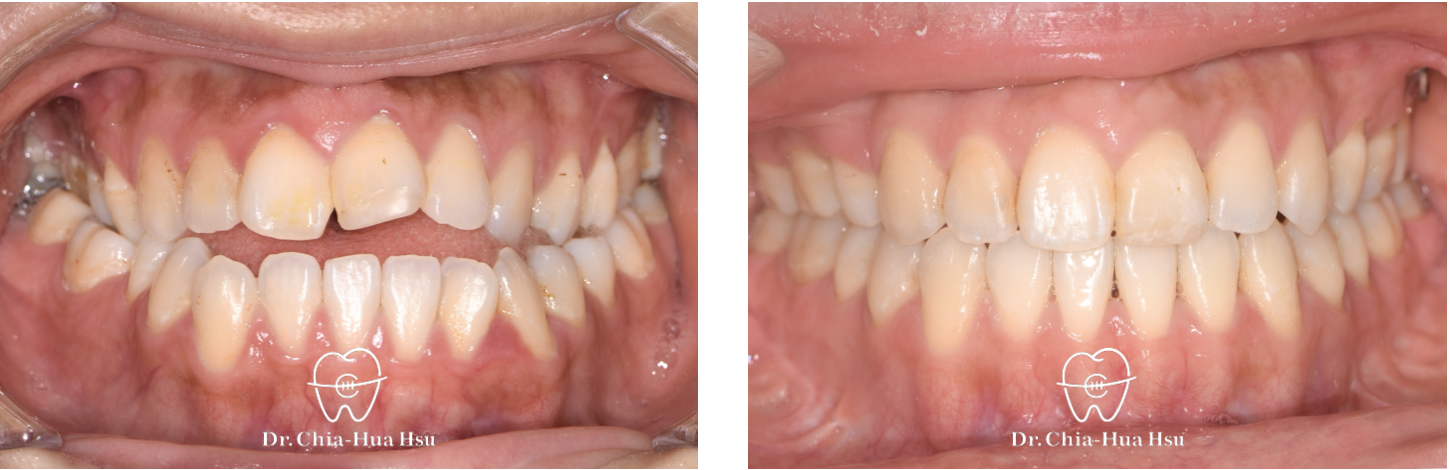

戽斗、前牙錯咬、開咬

成⼈矯正 | ⾦屬矯正 | 正顎⼿術

治療前

治療後